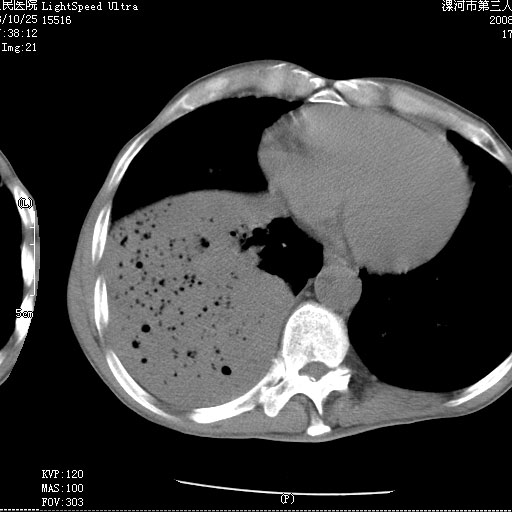

m 老年 发烧、呼吸困难,慢支、肺气肿多年;记的那次是下午大概17:38做的,晚上窒息死亡。

上面的层面就慢性支气管炎肺气肿、肺大泡,别的没有什么、也就不传了。

当时我怀疑:1、阻塞性肺不张早期 2、肺脓肿早期,望老师们发表意见

3、细支气管肺泡癌可以排除,病变以斜裂为界,呈大片状高密度影,内可见多发小气泡,表明有产气杆菌感染所致,内无明显的支气管“枯树枝征”表现,再结合其临床改变(细支气管肺泡癌临表表现重、影像表现轻)所以不符合细支气管肺泡癌(炎症型)的改变。

按肺叶分布,考虑肺不张

病变按肺叶分布,病变内可见多个小空腔影,未见充气支气管影,中间段支气管管腔肺窗示密度欠均匀,下肺支气管分叉处基底段支气管隐约可见,未见明显狭窄,中叶支气管通畅,

考虑:阻塞性肺炎伴小脓肿形成可能性大。(痰栓可能性大)

右下肺实变,内有弥漫分面小气泡而无支气管征,叶间裂前移,呈臌大之形,而无收缩之状,兼纵隔稍左行移,故。不支持不张,倒支持大叶肺叶,如楼上所说,小气泡不象残留之肺,不可以考虑产气菌感染吗。

阻塞性肺炎,肺脓肿形成。依据,右下支气管不通,大片实变形内可见小气泡。不支持肺不张。

坠积性肺炎合并右下肺膨胀不全